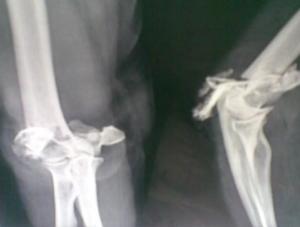

肱骨上端有三个骨骺,即肱骨头、大结节及小结节,顺序于1岁、3岁及5岁出现骨骺,于5~8岁三个骨骺融合成为肱骨上端一个骨骺,至19~21岁骨骺与肱骨干融合。因此,肱骨上端骨骺分离多见于7~18岁;以后成人可发生肱骨解剖颈骨折。由于肱骨上端在额状面上肱骨干骺端形成15°左右的后倾角,骨骺中心位于骺板的内后侧,因此,沿肱骨干向上传导的暴力作用于骺板,产生剪切应力,造成骨折线呈斜形,前外侧部分经过骺板面骨骺分离,后内侧部分经过干骺端时,形成一个三角形骨片,骨折线倾斜程度随年龄而异,年龄越大则骨折线经过骺板之横行距离越短,干骺端骨折片越大,且使倾斜面距离越长,骨折端越不稳定。